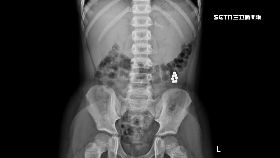

3歲童腹部見9個小白點 醫:破裂了

國內外發生多起孩童誤吞巴克球,造成腸道壞死的案例;一...